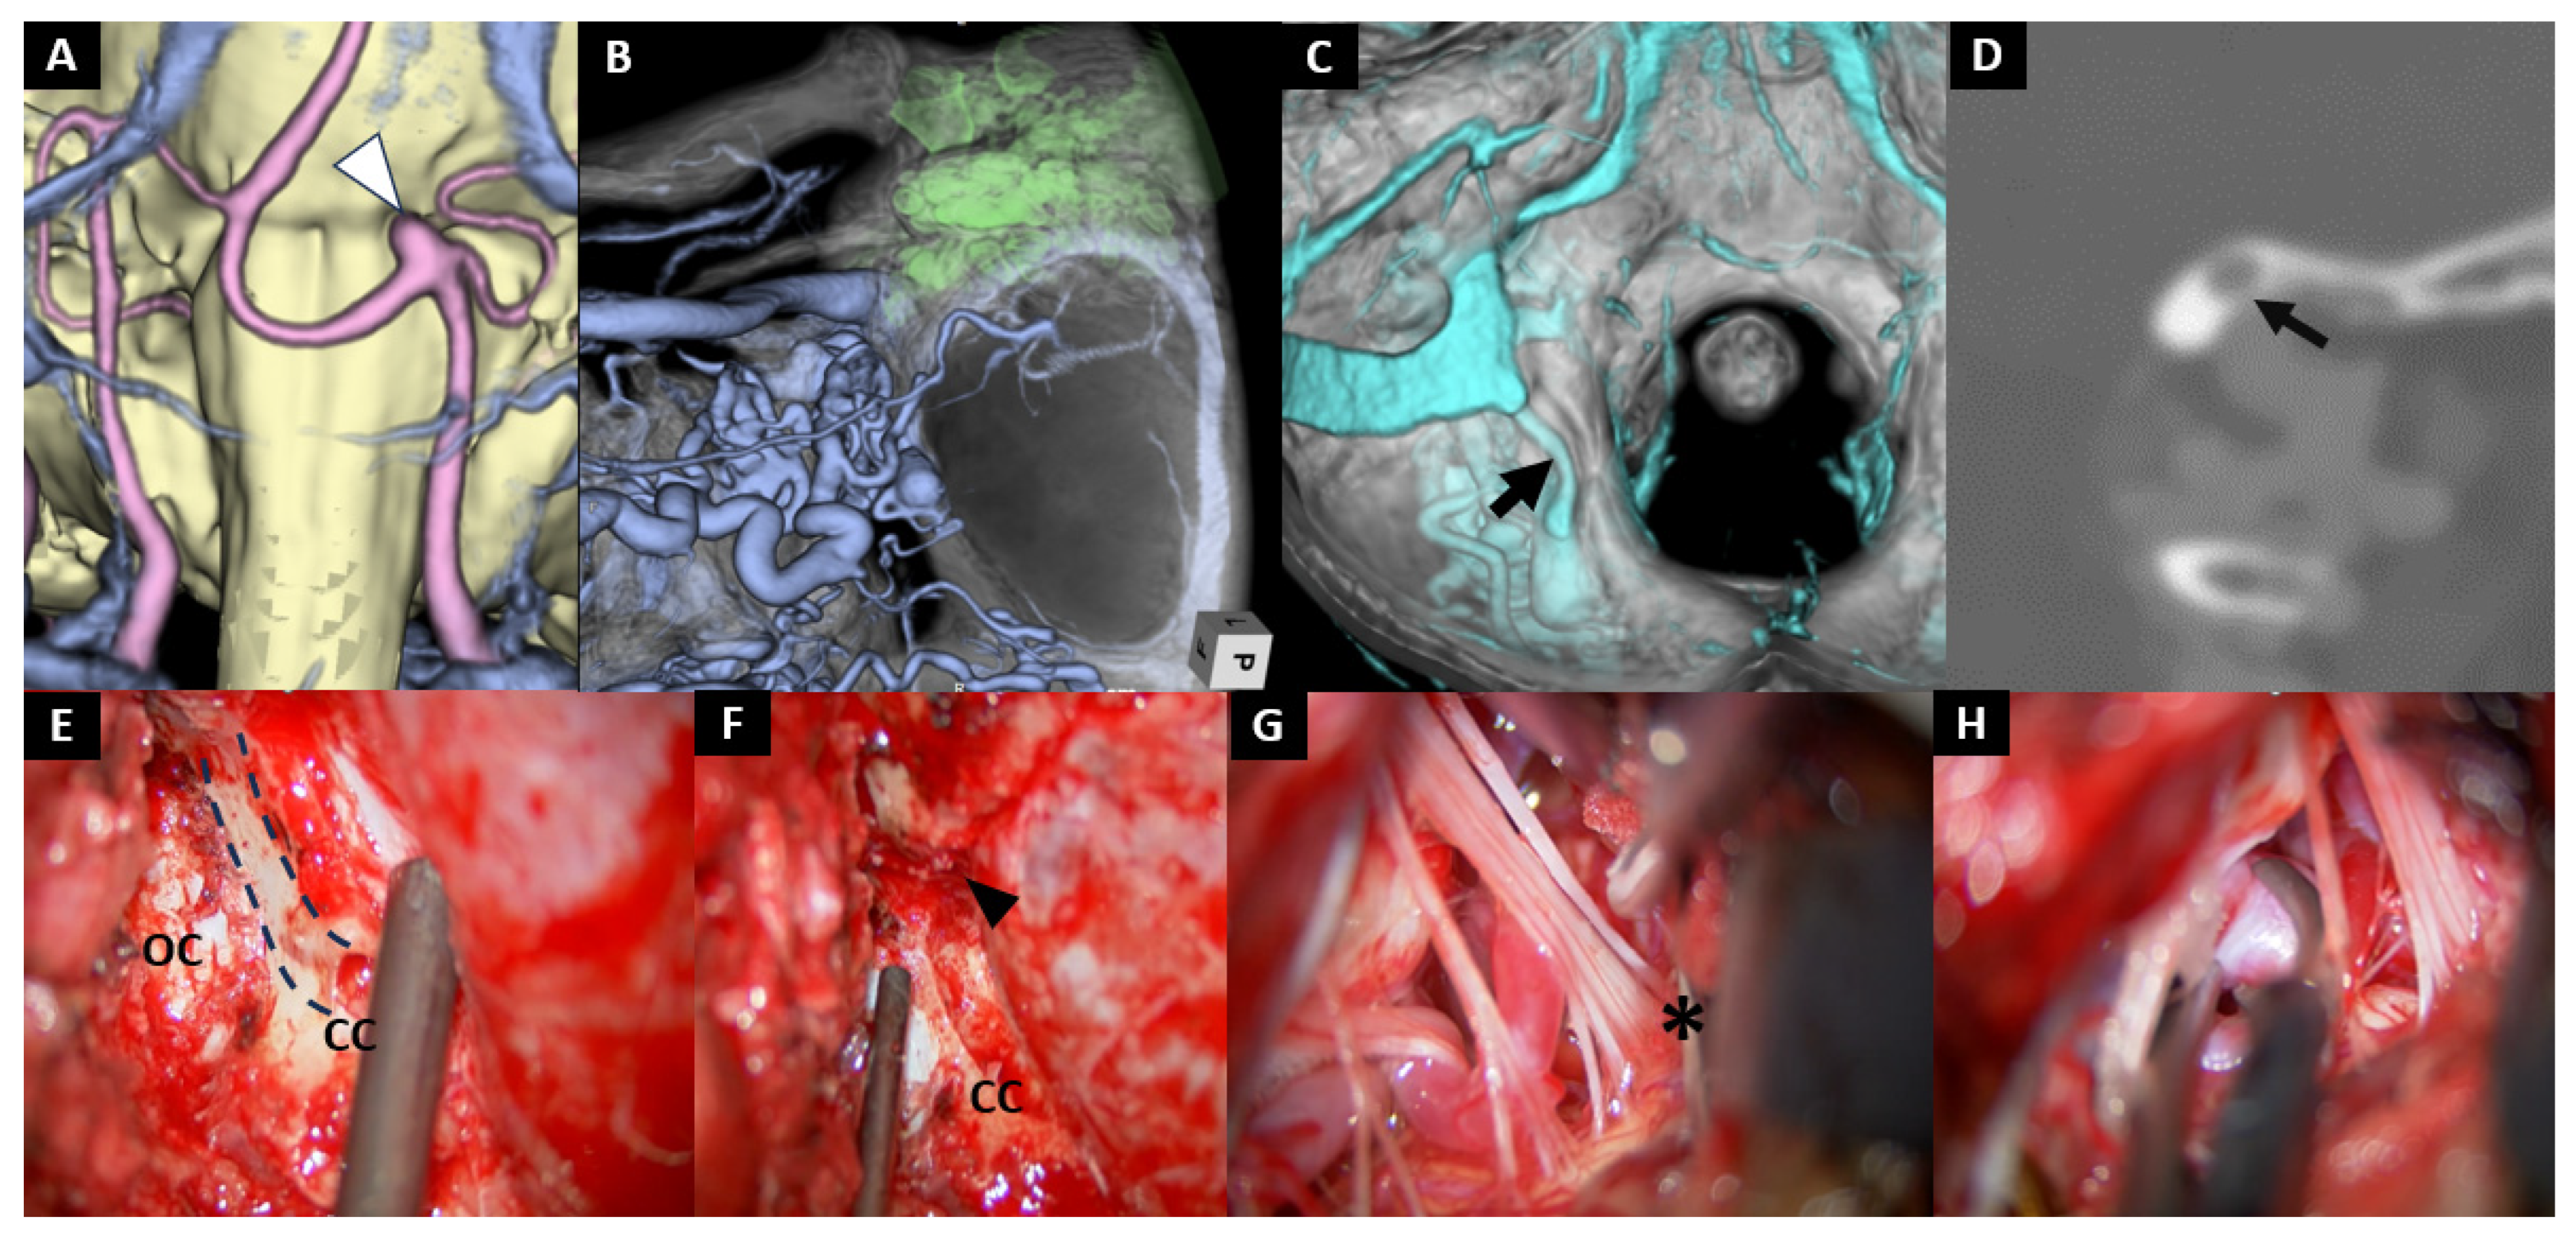

- Case No. 9

| 9 | 70 | F | saccular | VA-PICA | 4.5 mm | clipping | None | - | - | - | - | 0 |